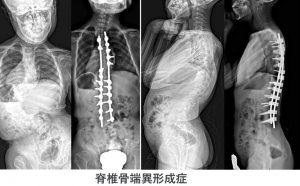

その他、様々な疾患にともなう特殊な側弯症(症候性側弯症)に対する治療も行っています。